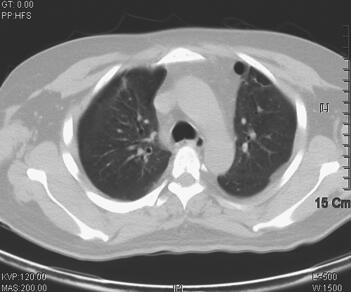

诊治经过:入科后立即予经口气管插管接呼吸机辅助通气,模式为BiPAP,参数为:FiO2 80%,Tinsp 0.95秒,PIP 30cmH2O,PEEP 15cmH2O,f 25次/分,呼吸急促,人机拮抗明显,予丙泊酚、咪达唑仑镇静,吗啡镇痛,间断维库溴铵肌松、扩容,亚胺培南-西司他汀钠1.0g静脉滴注,每8小时1次,莫西沙星400mg静脉滴注联合抗感染,乌司他丁、甲泼尼龙抑制炎症反应,氨溴索化痰,去甲肾上腺素维持血压及对症支持处理。治疗3天后患者临床症状改善不明显,高浓度给氧下氧饱和度维持在80%~85%,但患者部分炎症指标(BRT、CRP、PCT)进行性好转。考虑到患者病情危重,继续予机械通气支持,同时加大镇痛及镇静药物用量,减少患者氧耗。至4月8日血压仍需升压药维持,实验室检查NT-ProBNP 2084pg/ml,cTnI 0.35ng/ml,4月9日床边超声心动检查示心脏各个腔室大小正常,EF 45%,舒张功能减低,提示心功能不全,心肌损害。经过治疗,患者体温、BRT、CRP在入科治疗后即呈逐步下降趋势,至4月11日体温下降至正常范围,停用升压药物,血压维持120/75mmHg左右,呼吸机参数逐步下调,经皮氧饱和度维持在94%~96%左右。随后患者多次痰培养检出热带假丝酵母菌(4月7日、4月9日、4月11日、4月14日);因患者血液炎症指标逐渐下降,体温逐渐恢复正常,并无继发真菌感染的依据,考虑为定植菌可能,故未予抗真菌治疗,同时于4月12日停用亚胺培南-西司他汀钠,改用头孢哌酮-舒巴坦钠3.0g,每8小时1次,此后血常规检查血白细胞进行性升高,至4月17日白细胞计数22.72×109/L,并出现体温升高,至17日最高38.1℃,4月16日开始氧饱和度较前有所下降,波动在88%左右,尤其在吸痰后呼吸急促伴氧饱和度下降,遂予加大呼吸机支持力度,给氧浓度为60%,PEEP 14cmH2O,PSV 10cmH2O,RR 20次/分,Tinsp 1.1秒,SaO2维持在89%~94%。考虑已出现二重感染,继发肺部真菌感染可能性较大。4月17日加用氟康唑400mg每12小时1次,抗感染治疗,第2天400mg,每日1次。4月18日患者呼吸急促加剧,经加大镇静治疗及加强呼吸机支持均效果不佳,氧饱和度下降明显,只能维持在70%~80%左右;同时查血常规白细胞及CRP较前升高,两次半乳甘露聚糖试验(GM试验)回报结果阳性。临床考虑曲霉感染,予停用氟康唑,改用伏立康唑,继续加强镇静镇痛治疗,更改抗生素第2天晚上患者情况趋于稳定。之后患者体温下降,4月21日恢复至正常范围,呼吸情况逐渐改善,并能逐渐减少镇静药物剂量、下调呼吸机支持力度,同时WBC、CRP及PCT等炎症指标逐渐下降。4月25日复查胸部CT提示两肺感染较前吸收;4月25日复查超声心动图提示各个腔室大小正常,EF 65%,舒张功能减低;cTnI < 0.1ng/ml,NT-ProBNP 84pg/ml。4月26日发现胸壁皮疹,考虑为药物副反应可能,为伏立康唑的药物副反应所致,改用伊曲康唑继续抗曲霉治疗,患者皮疹逐渐消失,患者病情继续改善。至5月4日呼吸机改为CPAP模式,5月5日顺利停用呼吸机,予气管切开给氧,并停用全部鼻饲,经口进食,复查胸部CT提示双肺感染较前有所吸收,左下肺多发空洞形成,并转出ICU(图2)。5月10日,改为伏立康唑片剂序贯治疗,患者未出现皮疹以及其他不良反应,5月15日复查超声心动图提示各个腔室大小正常,EF 70%,舒张功能减低。5月20日肺功能检查提示重度限制性通气功能障碍。5月24日出院。6月8日复诊,患者自觉良好,无胸闷、气促,无发热,无咳嗽、咳痰,复查胸部CT双肺感染明显吸收、好转,左下肺空洞形成(图3)。继续服用伏立康唑片剂约2个月后停药,随访至今患者自觉良好,能够正常生活以及工作。

图2 2011年5月5日胸部CT示双肺感染较前明显好转,左下肺空洞形成